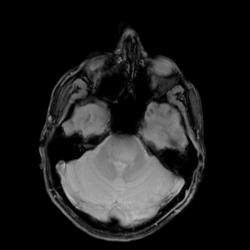

Спасибо за интересное наблюдение. Думаю, что это псевдотуморозная форма демиелинизирующего процесса, учитывая анамнез ( 4 месяца глазодвигательные нарушения), МР-томограммы, где в нижних отделах моста определяется округлой формы патологическая зона повышенного на Т2ВИ сигнала и пониженного на Т1ВИ. Ствол мозга при этом не деформирован, на постконтрастных МР-томограммах фактически нет накопления контраста. Конечно, может это и фибриллярная АСЦ ствола и другие заболевания, но я склоняюсь к этому диагнозу. Суважением Visus 07.

Если это демиелинизирующий процесс, как можно объяснить выход образования за передний контур среднего мозга? К тому же, ствол мозга пусть немного, но деформирован.

Выход образования за передний контур среднего мозга объясняется, вероятнее всего, экзофитным компонентом , который даже частично захватывает основную артерию, поэтому из своего диф.ряда на первое место теперь могу поставить опухолевое поражение. Надеюсь на Ваш ответ по данному случаю. С уважением Visus 07.

К сожалению, получить верификацию смогу, только если пациент придет на обследование повторно после лечения. На данный момент я считаю, что это опухоль глиального ряда.

Да, проанализировав МР-томограммы, эндофитно-экзофитный рост данного образования, подробные и четкие дополнительные комментарии, согласна с Вашим диагнозом. Спасибо, случай интересный и познавательный, с удовольствием читаю Ваши клинические наблюдения, с уважением, Visus 07.